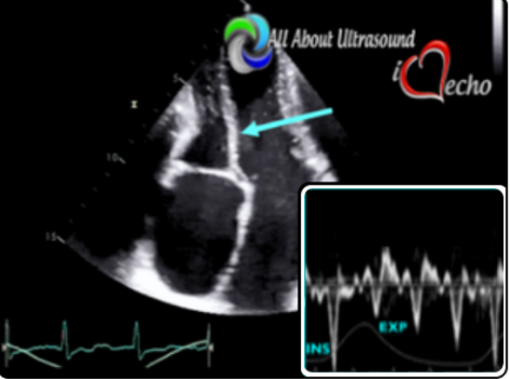

This online e-course is for sonographers interested in learning and reviewing correct techniques for performing echocardiography imaging and evaluation of constrictive pericarditis.